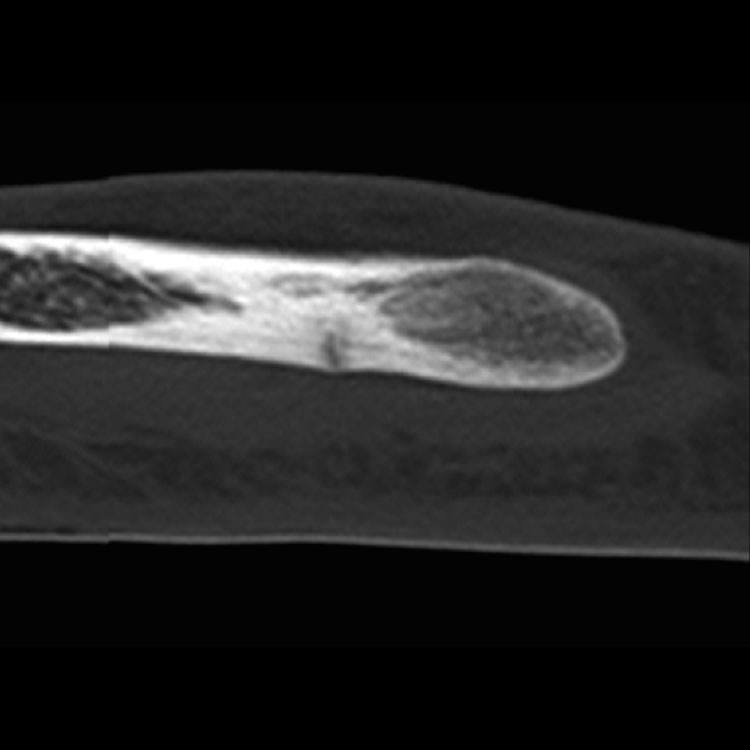

1. Accurate giagnosis 정확한 진단 : 피로반응이나 골절을 정확하게 진단하는 것이 효과적인 관리의 가장 중요한 요소.

5번째 중족골 (Fifth metatarsal): 지연 유합이나 재골절이 흔해 치료가 까다롭습니다. 엘리트 선수들에게는 **1차 고정술(수술)**이 표준으로 받아들여집니다.